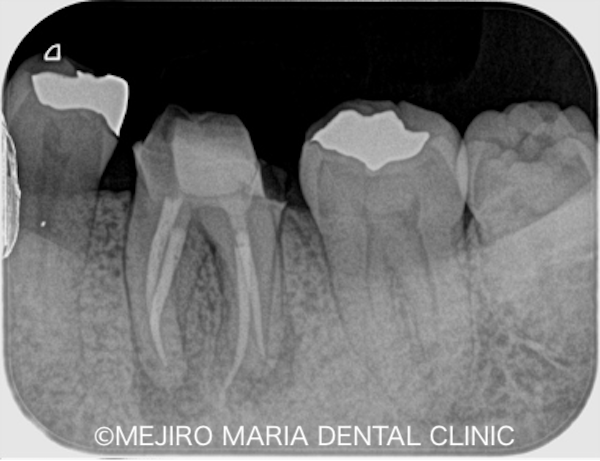

レントゲン写真で確認すると、金属の詰め物の下に虫歯を示す黒い影(写真中央の赤丸)と、歯の根の先端(根尖)にも黒い影が確認できました。歯髄診査を行って初診時の状態を調べたところ、歯髄に生活反応(神経が生きているか)は確認できず、歯髄は既に壊死を起こしている状態でした。